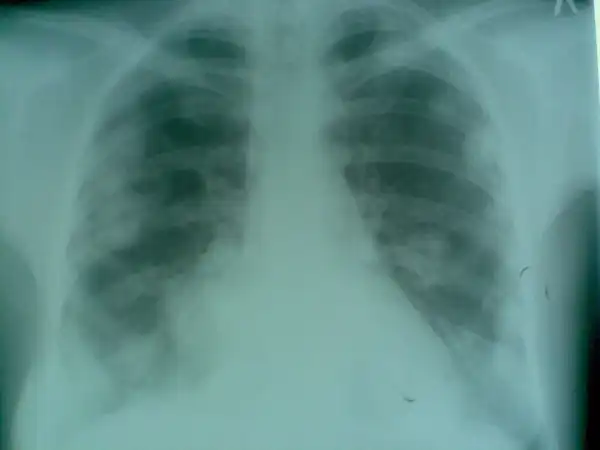

Пациент №2: